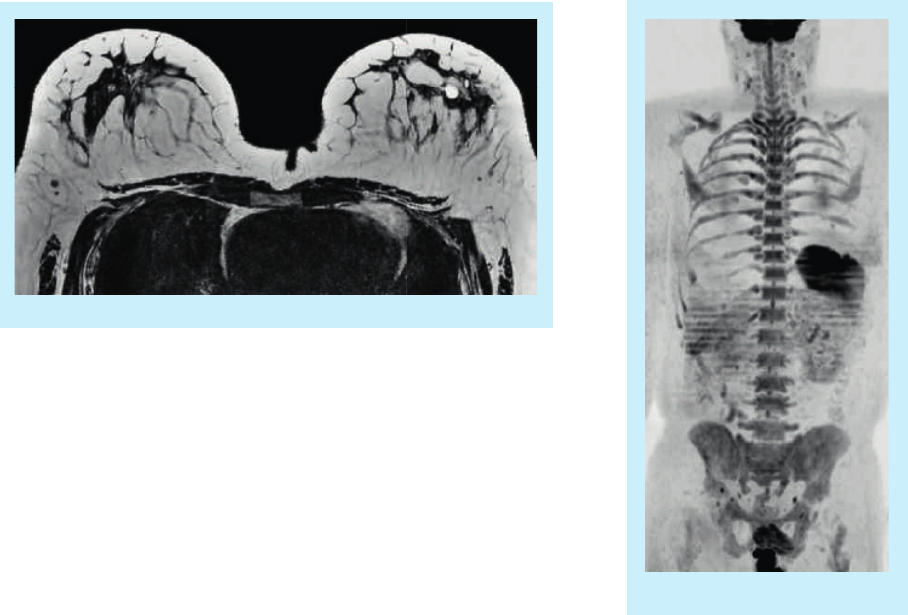

3D T2W VISTA Breast

High quality multi-station body DWI

Quantitative flow analysis of the aorta

Black Blood cardiac imaging with and without fat

suppression

Fast whole body

T2W imaging